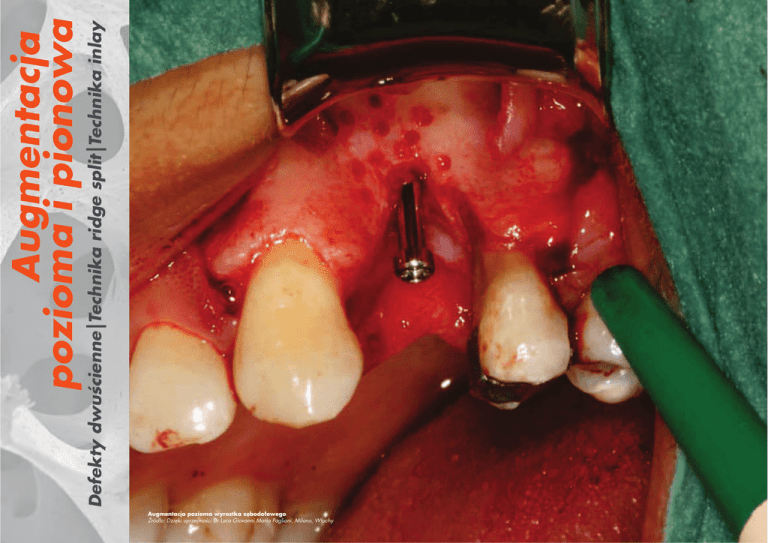

Defekty dwuścienne|Technika ridge split|Technika inlay

Augmentacja pozioma wyrostka zębodołowego

Źródło: Dzięki uprzejmości Dr Luca Giovanni Maria Pagliani, Milano, Włochy